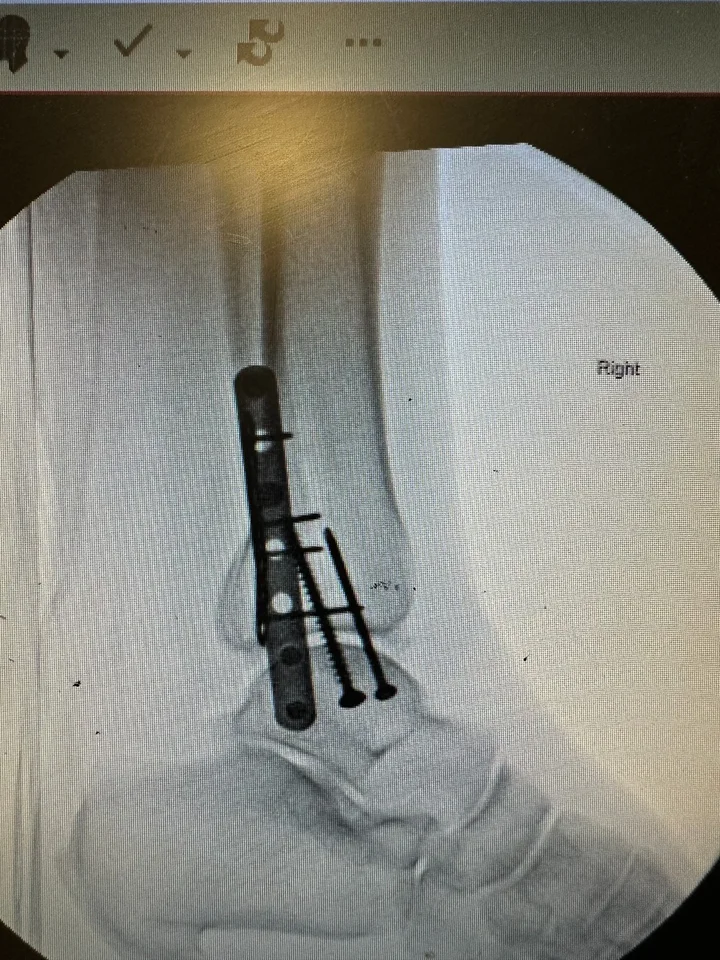

Easiest process and great company to deal with – Claim resolved within 6 weeks of accident and subsequent surgery Show details ·  1